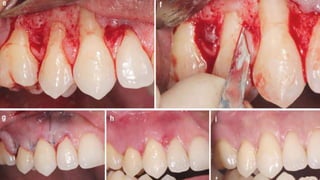

• #13 Class I gingival recessions– Baseline (a), recession depth of 3 mm (b), planning the papillary incisions (c), horizontal incisions performed as reported by Zucchelli and de Sanctis (d)

• #14 flap raised without releasing incisions (e), papillae de- epithelialization (f), flap coronally advanced and sutured as much as possible (with no tension) (g), 14-day follow-up (h), 4-month follow-up (i)